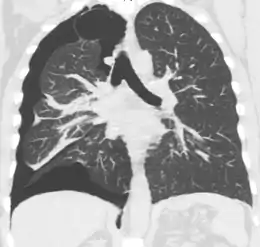

Chest X-ray

A plain chest radiograph, ideally with the X-ray beams being projected from the back (posteroanterior, or "PA"), and during maximal inspiration (holding one's breath), is the most appropriate first investigation.[30] It is not believed that routinely taking images during expiration would confer any benefit.[31] Still, they may be useful in the detection of a pneumothorax when clinical suspicion is high but yet an inspiratory radiograph appears normal.[32] Also, if the PA X-ray does not show a pneumothorax but there is a strong suspicion of one, lateral X-rays (with beams projecting from the side) may be performed, but this is not routine practice.[15][19]

Chest X-ray showing a pneumothorax on the right (left in the image), where the absence of lung markings indicates that there is free air inside the chest

Chest X-ray showing the features of pneumothorax on the left side of the person (right in image)

It is not unusual for the mediastinum (the structure between the lungs that contains the heart, great blood vessels, and large airways) to be shifted away from the affected lung due to the pressure differences. This is not equivalent to a tension pneumothorax, which is determined mainly by the constellation of symptoms, hypoxia, and shock.[13]

The size of the pneumothorax (i.e. the volume of air in the pleural space) can be determined with a reasonable degree of accuracy by measuring the distance between the chest wall and the lung. This is relevant to treatment, as smaller pneumothoraces may be managed differently. An air rim of 2 cm means that the pneumothorax occupies about 50% of the hemithorax.[15] British professional guidelines have traditionally stated that the measurement should be performed at the level of the hilum (where blood vessels and airways enter the lung) with 2 cm as the cutoff,[15] while American guidelines state that the measurement should be done at the apex (top) of the lung with 3 cm differentiating between a "small" and a "large" pneumothorax.[33] The latter method may overestimate the size of a pneumothorax if it is located mainly at the apex, which is a common occurrence.[15] The various methods correlate poorly but are the best easily available ways of estimating pneumothorax size.[15][19] CT scanning (see below) can provide a more accurate determination of the size of the pneumothorax, but its routine use in this setting is not recommended.[33]

Not all pneumothoraces are uniform; some only form a pocket of air in a particular place in the chest.[15] Small amounts of fluid may be noted on the chest X-ray (hydropneumothorax); this may be blood (hemopneumothorax).[13] In some cases, the only significant abnormality may be the "deep sulcus sign", in which the normally small space between the chest wall and the diaphragm appears enlarged due to the abnormal presence of fluid.[16]